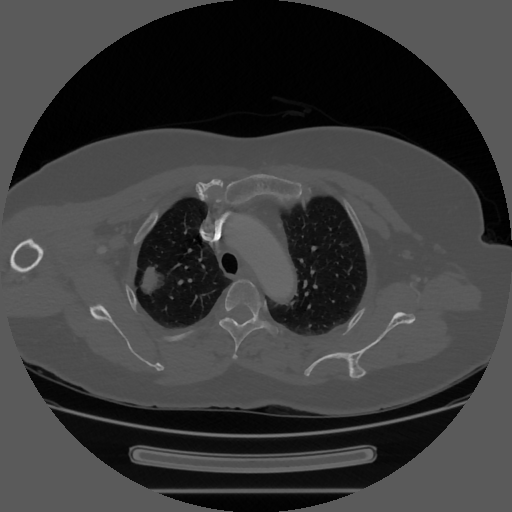

Lung cancer remains a leading cause of cancer-related deaths globally, with early detection and accurate diagnosis being vital for improving patient outcomes (tammemagi2019predicting). Computed tomography (CT) scans are crucial for identifying lung nodules, which serve as early indicators of malignancy (swanson2023patterns). Traditionally, radiologists examine these scans by evaluating nodule morphology and applying their medical expertise to produce diagnostic reports (osarogiagbon2023evaluation). However, this process necessitates radiologists to manually examine each subsequent CT image (hammer2019decision; lee2024read), which is time-consuming and susceptible to interobserver variability (driessen2025completeness).

Our experiments utilized two private datasets comprised of 1,616 and 386 axial lung CT slices (512×512 pixels). These datasets are carefully annotated to aid lung nodule detection, featuring bounding box masks, comprehensive morphological descriptions including lobar location, density, shape, margin, and indications of cavitation or vacuolation, and classifications of malignancy, categorized as pre-invasive, minimally invasive, or invasive adenocarcinoma. In addition to these private sources, we employed the public dataset LIDC-IDRI (samuel2011lung), including 1,018 lung CT scans with identical resolution. This dataset provides detailed lung nodule segmentation masks and semantic attributes such as size, margin clarity, density, and spiculation. Furthermore, it offers malignancy ratings ranging from 1 to 5, classifying scores above 3 as malignant and those below as benign.

| Nodule Image |

Image

Mask

|

|---|---|

| GPT-4o | The masked CT axial image reveals a solitary pulmonary nodule located in the right upper lobe of the lung. The nodule is well-circumscribed with smooth margins and demonstrates soft-tissue attenuation, consistent with a solid density. The shape is round to oval, with no evidence of spiculation or lobulation. There is no identifiable cavitation or internal vacuolization within the lesion. The surrounding lung parenchyma appears unremarkable, with no adjacent consolidation or pleural reaction. |

| Claude 3.7 Sonnet | Based on the axial CT image, there is a well-defined pulmonary nodule located in the left lower lobe. The nodule demonstrates solid density with smooth, well-circumscribed margins and maintains a round to oval morphology. No internal cavitation or vacuolation is evident within the lesion. The nodule appears homogeneous in attenuation without apparent calcification or fat density components. The surrounding lung parenchyma shows no immediate inflammatory changes or architectural distortion adjacent to the nodule. |

| InternVL | The image reveals a solitary pulmonary nodule located in the left upper lobe. The nodule exhibits a well-defined margin and a predominantly rounded shape. Its density appears homogeneous, contrasting with surrounding lung tissue. No cavities or vacuoles are observed within the nodule. The anatomical positioning suggests a discrete lesion, warranting further evaluation. |

| LLaVA | The lung nodule is located in the upper lobe. The nodule exhibits a solid, round shape with a thin, poorly defined margin. Its density is slightly increased compared to surrounding lung parenchyma. No visible vacuoles or cavities are present within the nodule. The red mask suggests this may be a preliminary diagnosis or visual aid for identification. Overall, it appears as a well-defined, solid mass in the upper lung lobe. |

| Medgemma | The masked region shows a solitary pulmonary nodule in the left upper lobe. The nodule is approximately 1.5 cm in diameter with solid density and smooth, well-defined margins. The shape is roughly round without evidence of internal vacuoles or cavitation. |

| Qwen2.5-VL | The lung nodule is located in the right lower lobe, appearing as a well-defined, homogenous, slightly hypodense mass with smooth margins. It has a round to oval shape without visible vacuoles or cavities. The findings are consistent with a benign lesion, though further evaluation is recommended. |

| MedR1 | The axial CT scan shows a well-defined, oval-shaped nodule in the right upper lobe. The nodule has homogenous density without cavitation or air bronchograms. Margins are smooth and well-defined without irregularities. No signs of vacuoles or cystic spaces are present. The location is typical for lung nodules. No associated abnormalities like pleural effusion are seen. Findings suggest a benign nodule, though further imaging/biopsy is recommended. |

| LungNoduleAgent | The lung nodule is located in the right upper lobe. It appears to have a part-solid density with around or oval shape and lobulated margins. The nodule demonstrates well-defined spiculation at the lung nodule interface. There are no air bronchograms or cavities present within the nodule. Additionally, there is an adjacent vascular convergence sign and pleural indentation noted. |